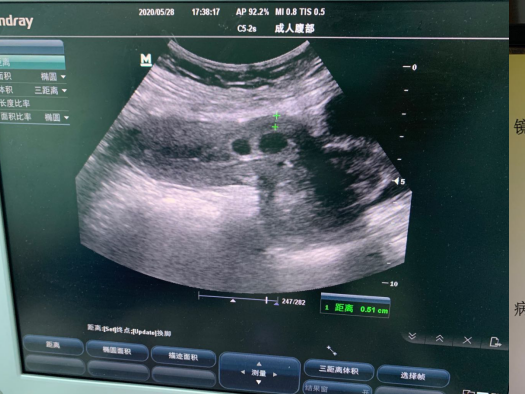

5月28日,佳木斯大學(xué)宏大醫(yī)院婦科收治了一名由富錦市緊急轉(zhuǎn)入我院年僅29歲卻有3次剖宮產(chǎn)手術(shù)史的患者。主要癥狀為停經(jīng)后陰道大量流血1天,入院彩超檢查顯示:子宮前壁下段近切口處囊性暗區(qū),3.0cm×1.4cm,下段切口肌層厚約0.5cm,瘢痕妊娠待排,盆腔積液,血HCG>50,000mIU/ml。

我院科教院長(zhǎng)、婦產(chǎn)科專家盧北燕、婦科主任劉小立帶領(lǐng)婦科團(tuán)隊(duì)認(rèn)真分析患者病情,入院診斷為:剖宮產(chǎn)術(shù)后子宮瘢痕妊娠。為了保留患者的生育功能,確保患者生命安全,我院婦科在患者入院第一天行子宮動(dòng)脈栓塞介入手術(shù),隔日于全麻下行宮腔鏡檢查術(shù)+宮腔鏡剖宮產(chǎn)瘢痕妊娠病灶切除術(shù)。術(shù)后病理送檢組織為妊娠絨毛、滋養(yǎng)細(xì)胞、蛻膜及凝血組織?;颊咝g(shù)后恢復(fù)良好,三天出院。